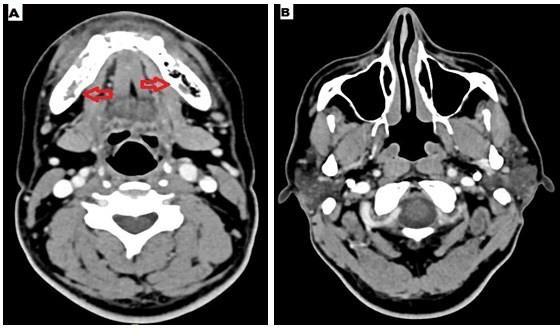

Case 2: He is a 46 years old male presented with pain and swelling of bilateral jaw. He was diagnosed with mild Covid-19 five months ago and received dexamethasone 6mg twice a day followed by once a day for 10 days. There was no history of prior dental procedures. No sinus pain or discharge was present. Sinus endoscopy was unremarkable. HbA1C was 11.2%. Imaging showed bilateral mandibular osteomyelitis (Figure 3) and underwent debridement. Histopathology from the debrided tissue showed broad aseptate fungal hyphae with obtuse angle branching associated with bony and angioinvasion suggestive of mucorales. Few actinomycotic colonies are also found interspersed in the tissue biopsied. Culture was negative for fungal organisms. He was started on injection amphotericin b deoxycholate due to cost constraints and developed acute kidney injury after 5 days. As the disease was limited to bone and he could not tolerate injection amphotericin b for more than 5 days we switched him to tablet posaconazole. Trough concentration was measured after 7 days and found to be 1308 ng/ml. He did well with oral therapy and completed 3 months of posaconazole.

Figure 3 A - CT mandible- bilateral mandibular osteomyelitis with erosion of the cortex, B - CT paranasal sinuses- normal.